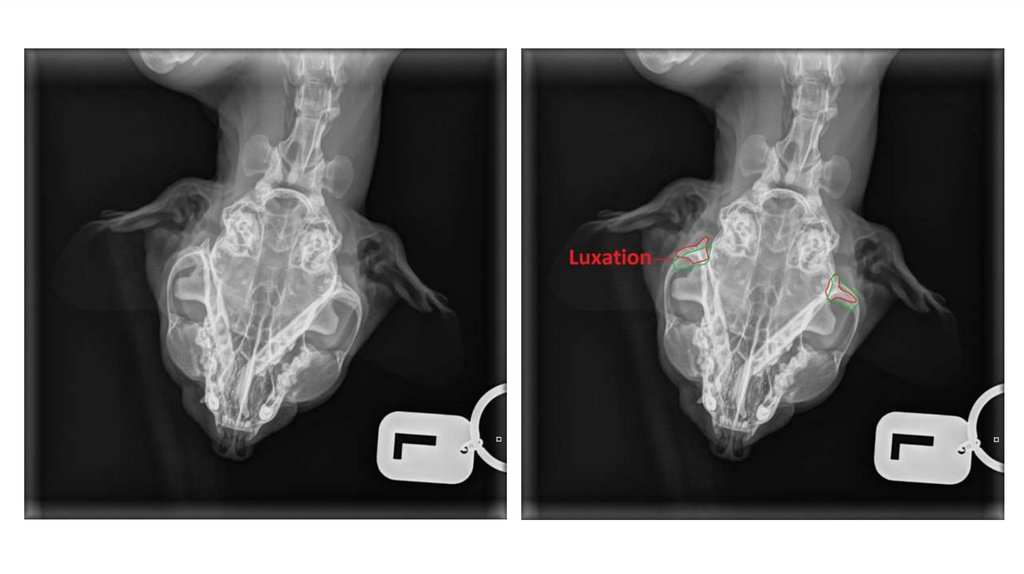

Диагностика: диагноз ставится на основании анамнеза, клинических признаков

и рентгенологического исследования (при необходимости КТ).